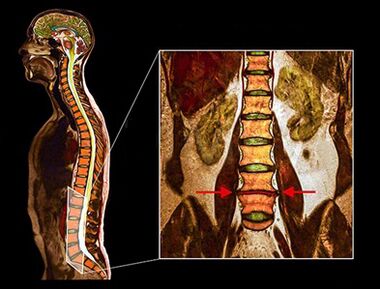

Diagnostics

- The above diagnostic methods are usually sufficient for diagnosis of osteochondrosis, but accurate diagnosis requires the use of visualization method.

- MRI - This diagnostic method allows you to explain the degree of degeneration, the presence of bone fractures, stenosis disc hernia.Often MRI studies are needed in preparation for surgical treatment to accurately determine the location of the degeneration disc and plan surgery.

Studies have shown that MRI outcome with moderate or significant disc deterioration was found when scanning the patient, either with severe and minimal pain or a lack of pain.In addition, many painful conditions may not appear in MRI.For this reason, the diagnosis cannot be made exclusively based on visualization outcomes, and diagnosis verification is only possible based on the entire clinical and instrumental examination method.